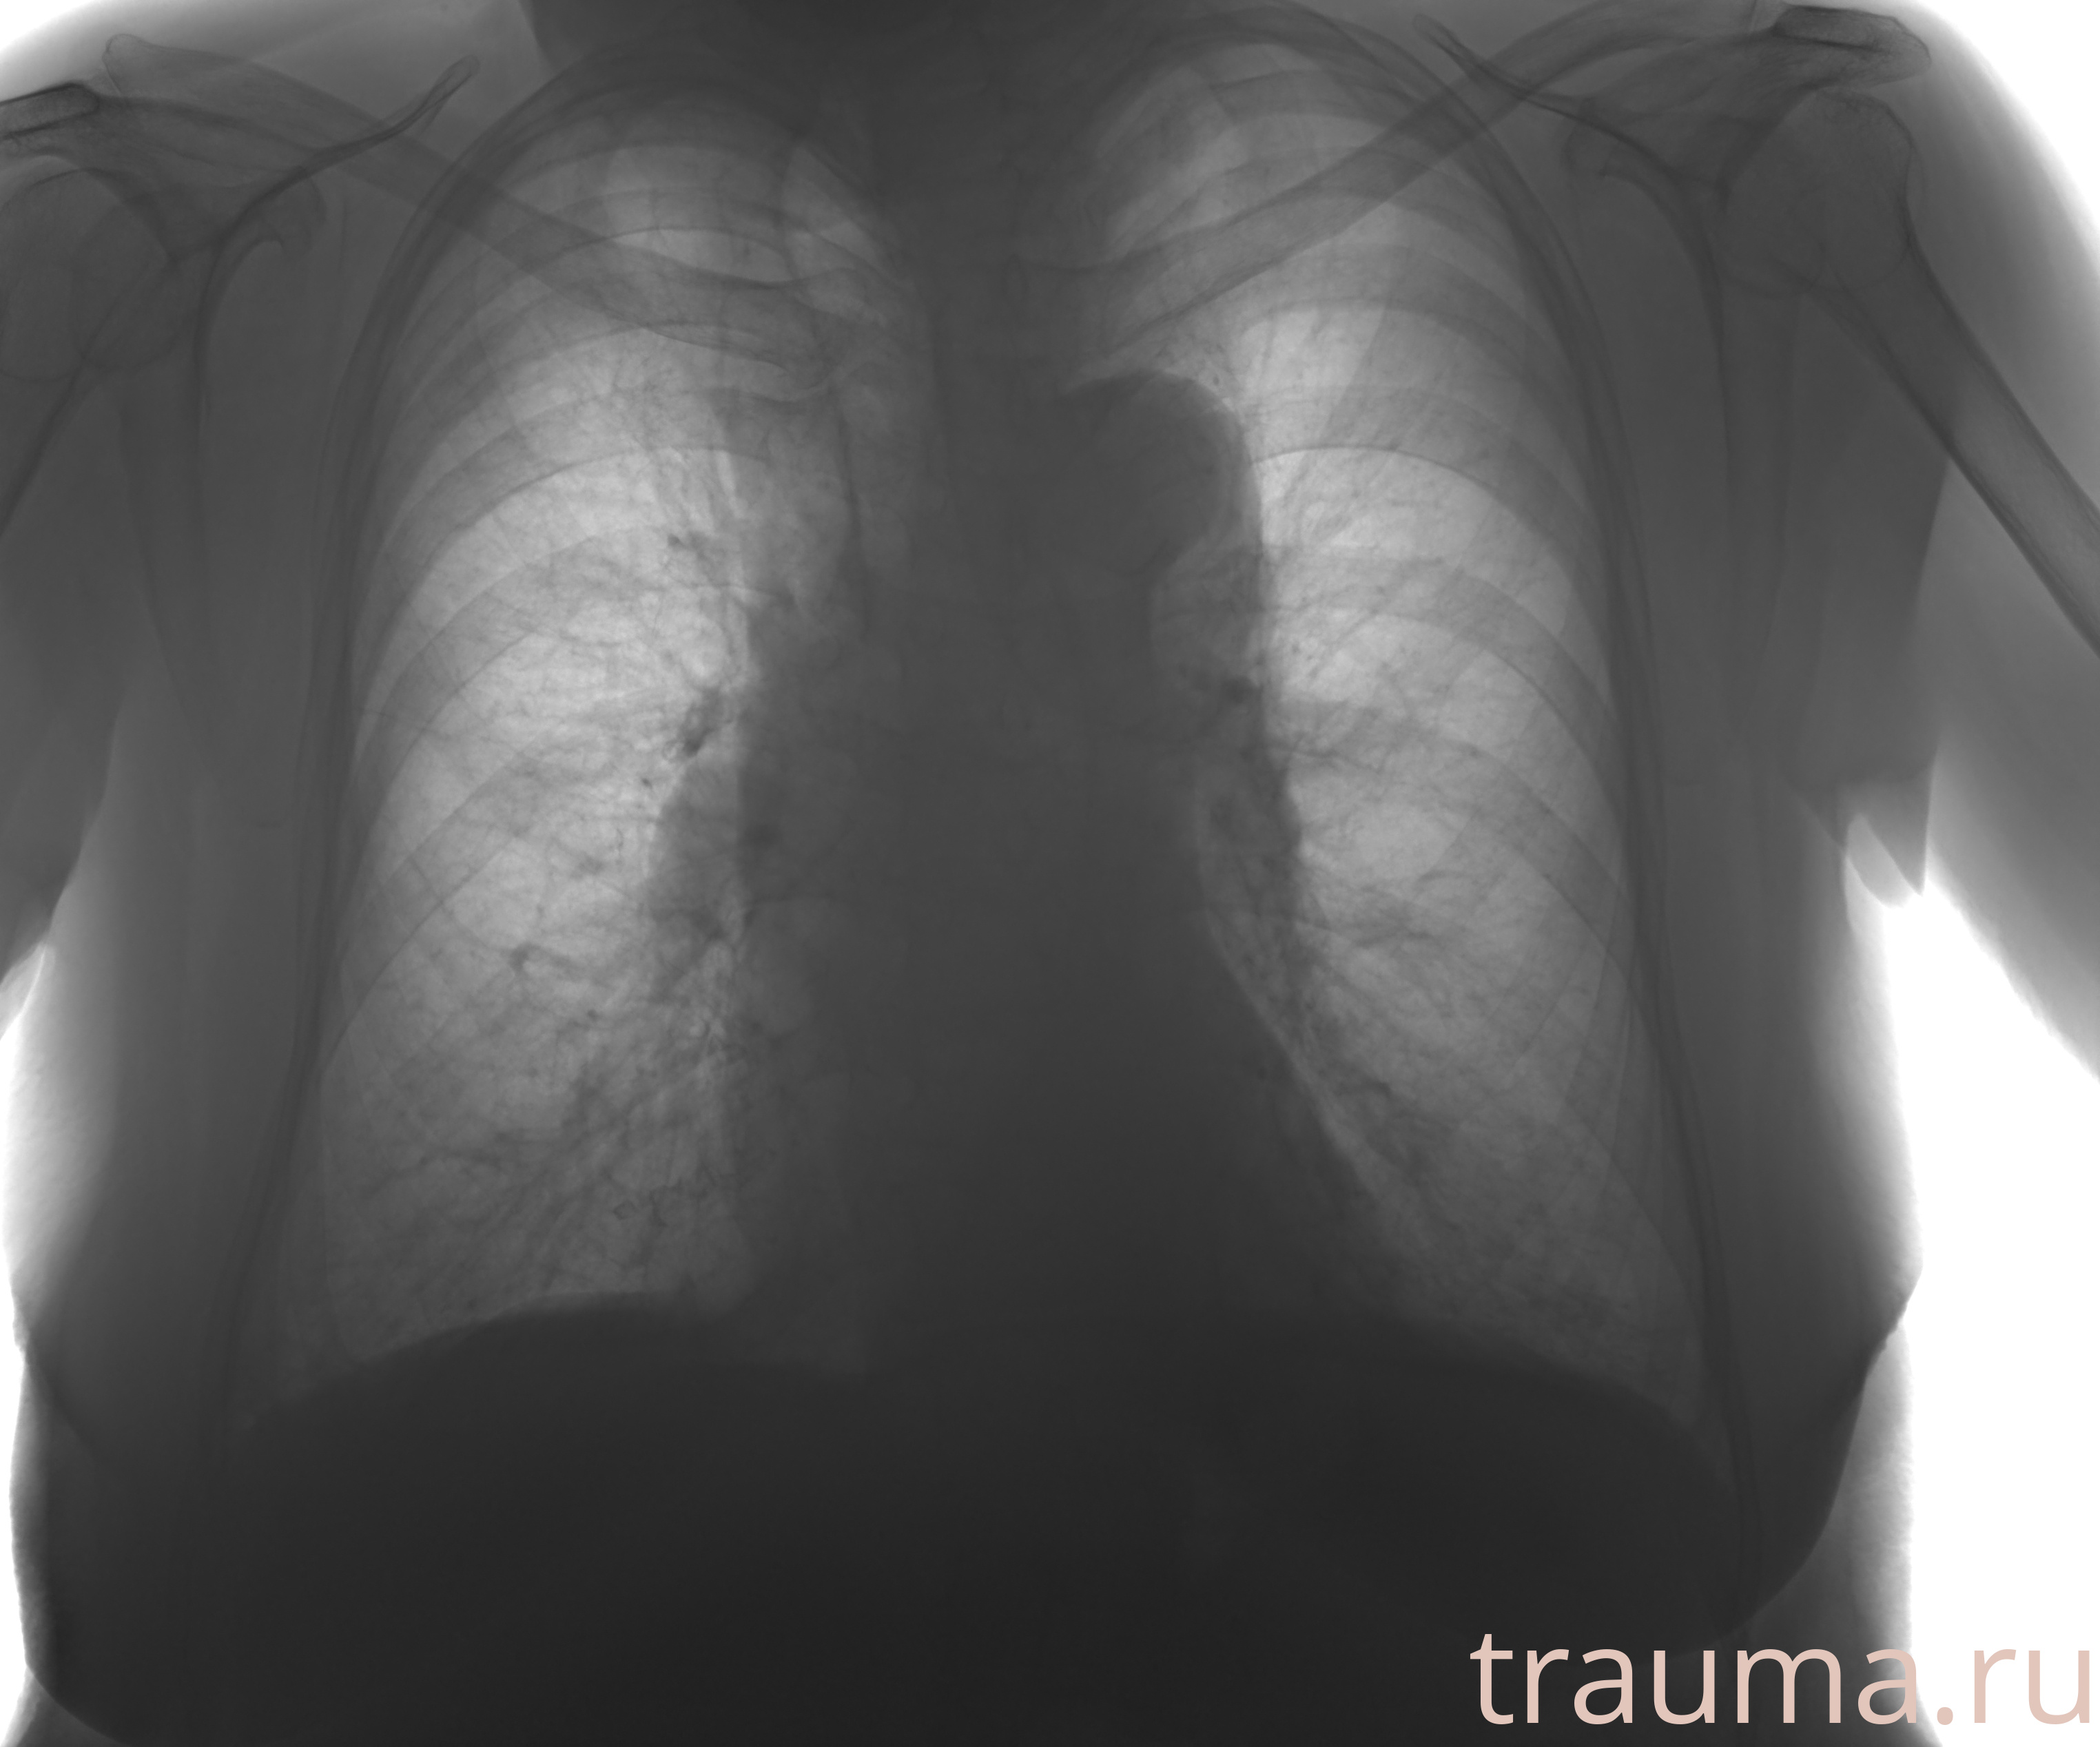

Рентген на дому: по вашему адресу приезжает врач-рентгенолог, травматолог-ортопед с мобильным рентгеновским аппаратом, проводит диагностику травмы или заболевания, делает необходимые рентгенограммы, дает рекомендации по дальнейшему лечению. Получить качественные снимки в домашних условиях возможно благодаря уникальной методике, разработанной МосРентген Центром для института  Склифосовского